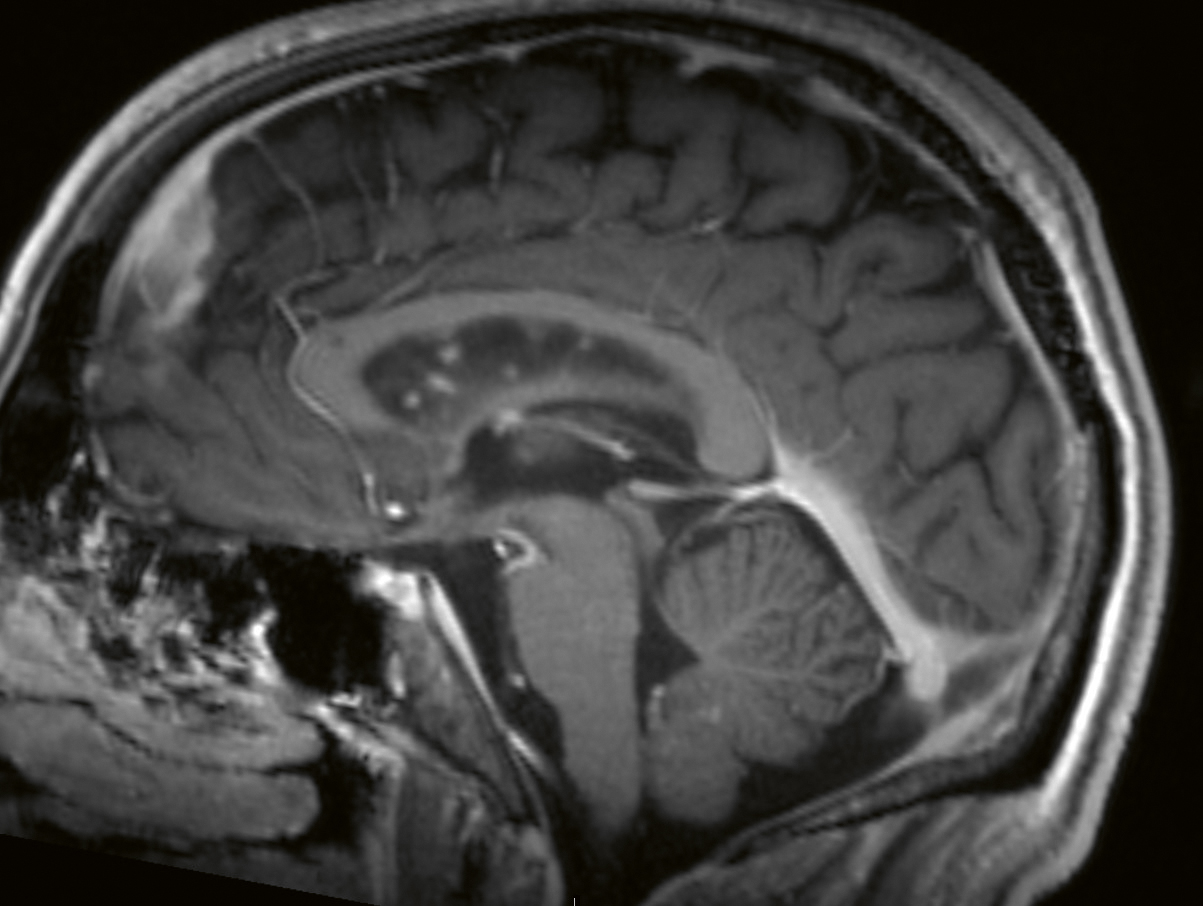

Vid misstanke om neurosarkoidos är det viktigt att utföra en MR-undersökning av hela CNS, det vill säga både hjärnan och ryggmärgen. Dessutom bör MR alltid göras med kontrast. Leptomeningeal uppladdning, både diffus och nodulär i skallbasen, är det vanligaste MR-fyndet (T1-viktad sekvens) vid neurosarkoidos, med en förekomst på 56 procent. Vid spridning till de basala hjärnhinnorna kan man även se påverkan på de lägre kranialnerverna (Figur 1 och 2). Pakymeningit är mindre vanlig som isolerat fynd vid neurosarkoidos (Figur 3) [32, 33]. Kontrastuppladdning i de drabbade kranialnerverna ses ibland vid MR, men inte alltid [34]. MR av hypofysen visar oftast en multi­fokal förstoring och kontrastuppladdning av främre hypofysen och infundibulum, och ibland även av hypo­talamus [35, 36]. Peri­ventrikulära och djupa vitsubstanslesioner, som är högsignalerande på FLAIR- och T2-sekvenser, är vanliga vid neurosarkoidos och kan vara svåra att särskilja från vaskulära förändringar [37]. Hydrocefalus och tumörliknande förändringar förekommer, men är ovanliga fynd vid neurosarkoidos [37]. Vid misstanke om vaskulit bör susceptibilitetsviktad MR-sekvens (SWI), kärlväggs­avbildning och konventionell angiografi utföras. Framträdande medullära vener har beskrivits som ett specifikt fynd vid neurosarkoidos [38].

Figur 1. MR hjärna, T1-viktad, Gd+. Bilden visar leptomeningeal uppladdning i bakre skallgropen, främst längs hjärnstammen men också i lillhjärnsfåror och basala cisterner med engagemang av kranialnerver.